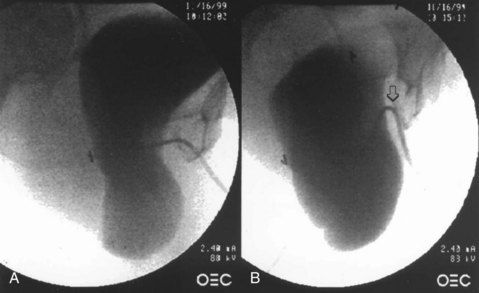

Positioning and preparation of the patient to allow abdominal and vaginal access initiate the repair. The bladder is drained. The retropubic space is entered through either a low midline or transverse incision. Additionally, this may be accomplished laparoscopically. The bladder neck, symphysis pubis, endopelvic fascia, ATFP, and obturator fascia should all be clearly identified. The normal site of normal vaginal attachment on the pelvic side wall from the interior aspect of the superior pubic ramus to the ischial spine is then identified. The surgeon’s nondominant hand is placed into the vagina and used to elevate the lateral superior vaginal sulcus to its site of normal attachment along the course of the ATFP. With the bladder retracted medially, four to six interrupted nonabsorbable sutures are placed at 1-cm intervals through the ATFP extending from the ischial spine to the pubic bone. These sutures are then placed in the appropriate location in the lateral wall of the vagina. Care is taken to avoid paravaginal veins, which commonly course through this area. Elevating the vagina to its normal anatomic position to localize suture placement site may facilitate vaginal suture placement. After the sutures are tied, cystoscopy must be performed to confirm ureteral patency and the absence of intravesical sutures. The incision is closed and the catheter is left indwelling.

Figure 72–22 Abdominal paravaginal repair. Paravaginal defect repair as viewed from the retropubic space: approximation of the pubocervical fascia medially to the arcus tendineus fasciae pelvis laterally with 2-0 braided nonabsorbable suture. Note the vertical orientation of the vaginal vessels in relation to the transverse orientation of the bladder vessels. Inset shows suture being passed beneath the vaginal vessels to ensure generous purchase of pubocervical fascia and control of hemostasis.